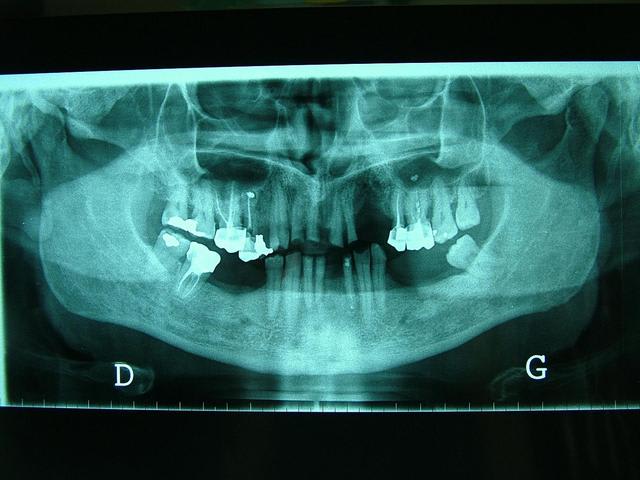

Homme de 57 ans avec DV effondrée.

faut voir comment sont ses dents residuelles,mobiles ou pas,il y a un grand manque osseux d'un (coté droit écran,je ne sais dans quel sens tu as mis la pano )extraction recente?

Pano correspond aux modèles ????

Pano inversée

Oui...egressé et usée. Regarde l'os alveolaire de la pano.

Regarde aussi le collet de la 43 et 46...

De toute façon il n'y a pas perte de DV si il n'y a pas perte de calage posterieur...

Je confirme il y a un calage posterieur...presque pas de perte de DV. Donc la distance "maxillo-mandibulaire" n'a pas diminuée.

Il y a qu'a regarder la dimension verticale de repos...on saura si il y a variation de DV.